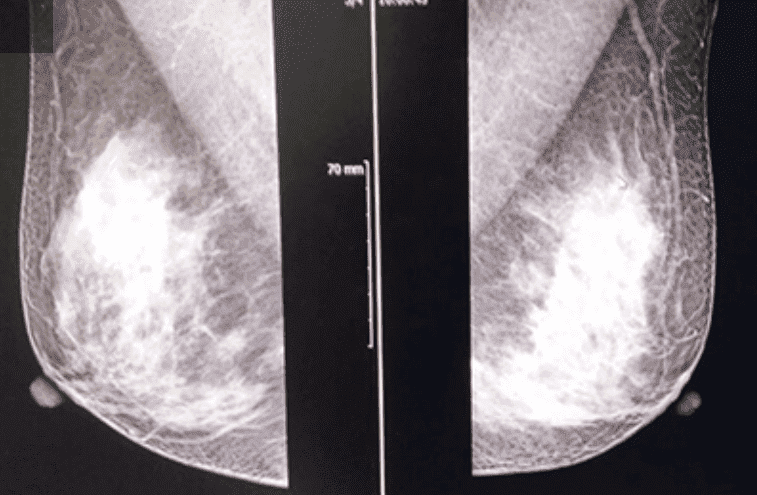

유방암

유방암이란 ?

유방은 여러 종류의 세표들이 모여 있는 장기입니다. 이 세포들 각각에서 암이 발생할 수 있으므로 유방암의 종류도 다른 장기의 암에 비해 많은 편입니다.

하지만 대부분의 유방암은 유관에서 기원하여 이를 관암종이라고 합니다.

유방암 검진

유방암 검진의 목적

조기유방암을 발견하여 조기치료로 생존율을 높이기 위함입니다.

새로운 유방암 검진 방법 (미국 암학회 권고)

기존의 유방암검진을 보완하기 위하여 새로운 권고안이 제시되었습니다.

20-39세 여성

• 전문유방진찰 : 1-3년마다

• 유방자각 ( breast awareness) : 아래 항목 참고

40세 이상 여성

• 유방촬영 : 매년

• 전문유방진찰 : 매년

※ 유방암 발생율을 증가시키는 위험요소가 있는 여성은 검진의사와 상의하는 것이 좋고, 더욱 철저한 검진을 받는 것이 좋습니다.